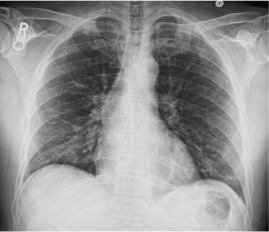

Стандартная РГ имеет низкую чувствительность в выявлении начальных изменений в первые дни заболевания и не может применяться для ранней диагностики. Информативность РГ повышается с увеличением длительности течения пневмонии. Рентгенография с использованием передвижных (палатных) аппаратов является основным методом лучевой диагностики патологии ОГК в отделениях реанимации и интенсивной терапии (ОРИТ). Применение передвижного (палатного) аппарата оправдано и для проведения обычных РГ исследований в рентгеновском кабинете. В стационарных условиях относительным преимуществом РГ в сравнении с КТ являются большая пропускная способность. Метод позволяет уверенно выявлять тяжелые формы пневмоний и отек легких различной природы, которые требуют госпитализации, в том числе направления в ОРИТ.

КТ имеет высокую чувствительность в выявлении изменений в легких, характерных для COVID-19. Применение КТ целесообразно для первичной оценки состояния ОГК у пациентов с тяжелыми прогрессирующими формами заболевания, а также для дифференциальной диагностики выявленных изменений и оценки динамики процесса. КТ позволяет выявить характерные изменения в легких у пациентов с COVID-19 еще до появления положительных лабораторных тестов на инфекцию с помощью МАНК. В то же время, КТ выявляет изменения легких у значительного числа пациентов с бессимптомной и легкой формами заболевания, которым не требуется госпитализация. Результаты КТ в этих случаях не влияют на тактику лечения и прогноз заболевания при наличии лабораторного подтверждения COVID-19. Поэтому массовое применение КТ для скрининга асимптомных и легких форм болезни не рекомендуется.